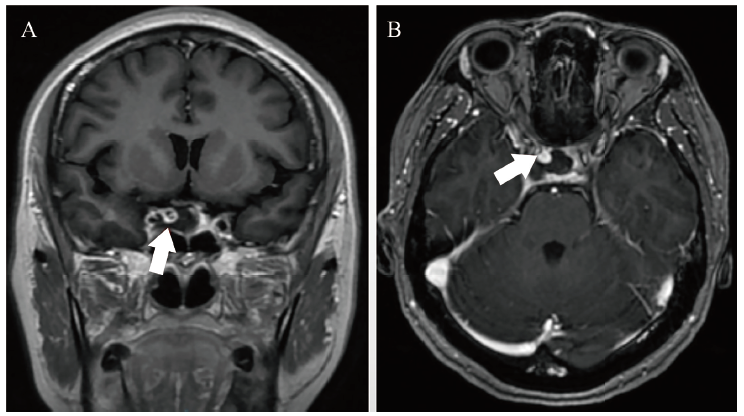

根据欧洲抗风湿病联盟/美国风湿病学会2019年发布的SLE分类标准,结合患者症状、体征、实验室检查结果,诊断为SLE、SLE血液系统损伤、狼疮肾炎、神经精神性SLE。SLEDAI-2000评分20分,治疗方案为口服甲泼尼龙40 mg/d,口服硫酸羟氯喹200 mg每日2次,考虑患者在外院使用过环磷酰胺且累积剂量达1.4 g,因此仅予0.6 g环磷酰胺静脉滴注诱导缓解治疗,同时予兰索拉唑、阿法骨化醇、碳酸钙D3支持治疗。1月22日晚患者开始出现头痛、呕吐及眼球向内、向上活动受限,予眼科会诊,完善光学相干断层成像(OCT)提示,双眼浆液性视网膜剥离,荧光素血管造影(FFA)提示右眼黄斑上方可见渗漏点。同时行头颅MRI示右侧海绵窦区见一结节状异常信号灶(图2),呈现不均匀性血管流空影,最大直径达23 mm,考虑患者颅内动脉瘤较大且已经压迫动眼神经引起相应症状,随时有破裂风险,经疑难病例讨论后,在积极规范治疗SLE的同时转神经外科进行手术治疗。

图2 一例SLE伴颅内动脉瘤致右眼睑下垂患者的头颅MRI结果

注:右侧海绵窦区见一结节状异常信号灶(箭头所示),其中A为头颅MRI冠状位影像,B为头颅MRI水平位影像。